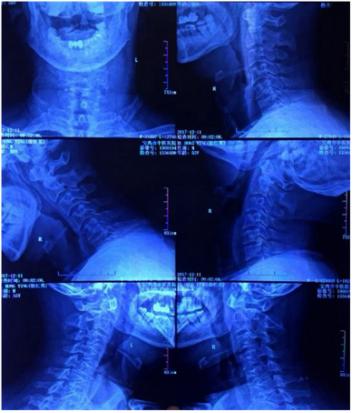

影像资料

从影像资料可以看到一侧颈3-4椎间孔狭窄,患者出现的一侧神经根型症状和影像资料相符。临床上,一般建议此类患者做神经根的牵拉实验,如果实验呈阳性的话,基本可以诊断为神经根型颈椎病。

仔细看患者影像资料,过仰过伸位、中立位的检查都显示颈椎曲度还可以。临床上,有的患者颈椎曲度没有发生变化,但是神经根管儿处的钩椎关节有增生。对于此类患者,一般建议做颈椎的三维CT明确,多数时候可以看到钩椎关节神经根孔狭窄。